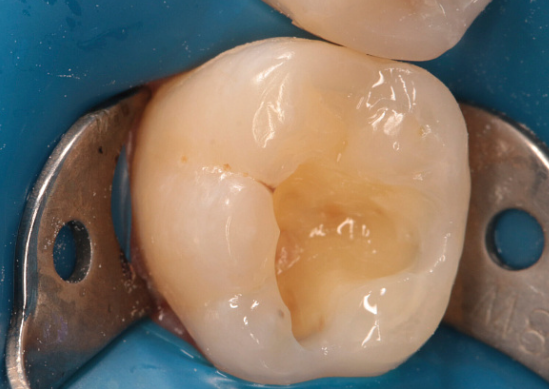

4 работы в портфолио

Манучарьянц Арутюн Артемович принимает в медицинском диагностическом центре MDC CLINIC (МДЦ КЛИНИК) в Москве. Стаж 8 лет. Специализируется на терапевтии и эндодонтическом лечении, по которым клиника оказывает 17 услуг. Имеет 4 работы до/после в портфолио. Квалификация специалиста подтверждена 3 лицензиями, сертификатами и наградами. Для уточнения дополнительной информации о специалисте или записи на прием можно позвонить по телефону